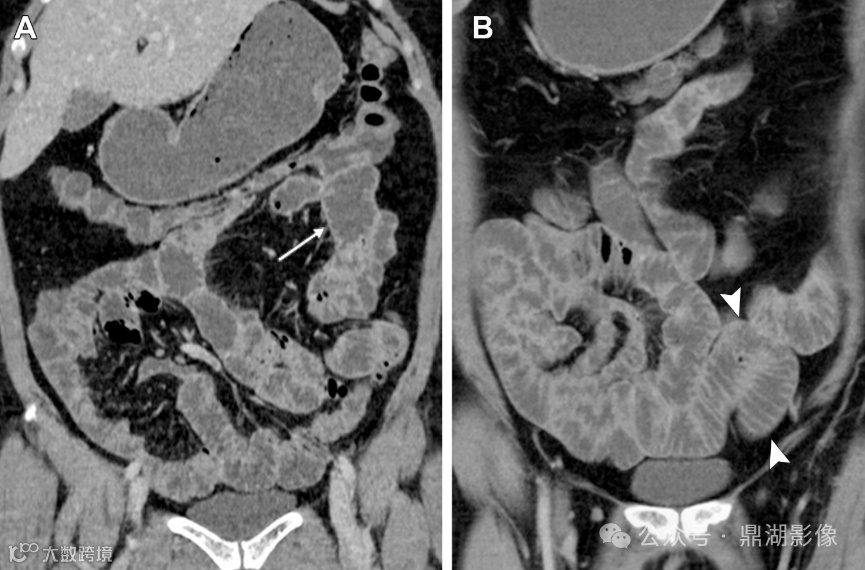

图2.患者,女,59岁,乳糜泻。静脉注射对比剂增强CT小肠造影冠状位图像显示小肠皱襞模式反转,表现为空肠皱襞数量减少(A中的箭头),这是由于绒毛萎缩所致;回肠皱襞数量增加(B中的箭头),代表回肠空肠化,这是对吸收不良的一种代偿。

空回肠皱襞模式反转

空回肠皱襞模式反转(称为回肠空肠化,空肠皱襞减少,回肠皱襞增加)是乳糜泻最特异的征象,文献报道其敏感性和特异性(阳性预测值和阴性预测值)接近100% 。 5cm距离内回肠皱襞数量多于空肠皱襞数量时,则被认为是阳性。

在CT和MR小肠造影图像上观察到每英寸(=2.54cm)肠段的皱襞少于或等于3个,则认为空肠皱襞密度降低。在重度乳糜泻中,空肠皱襞可能完全消失。在慢性炎症的情况下,回肠皱襞密度可能代偿性增加,定义为每英寸超过5个皱襞,以增加小肠表面积。皱襞数量的增加代表回肠对空肠吸收能力下降的一种适应。